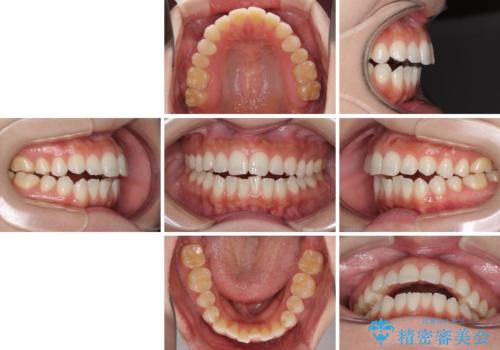

- 前歯の上下スペースによる話しにくさと顎への負担を気にして来院された患者様です。

インビザラインにより上顎の大臼歯を圧下し、上下の前歯の隙間を閉じていくこととしました。

上顎の奥歯を圧下させることで、上下前歯を接触させるように計画しました。

前歯が急に接触するようになり、慣れるまで時間がかかりましたが、前歯でものが咬めるようにもなり、患者様には大変満足していただきました。